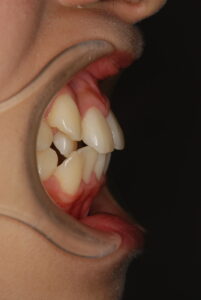

実際の症例紹介(20代女性/裏側ワイヤー矯正)

治療前

・主訴:八重歯と前歯の突出

・治療法:裏側からのワイヤー矯正(リンガル)

・治療期間:約1年半〜2年(目安)

・予想される副作用・リスク:装置装着後の違和感・疼痛、発音のしづらさ、一時的な咀嚼効率低下、ブラッシング不良によるむし歯・歯周病リスク など

※写真は代表的な症例です。口腔内の状態により治療法や期間は異なります。詳細は初診相談でご説明します。